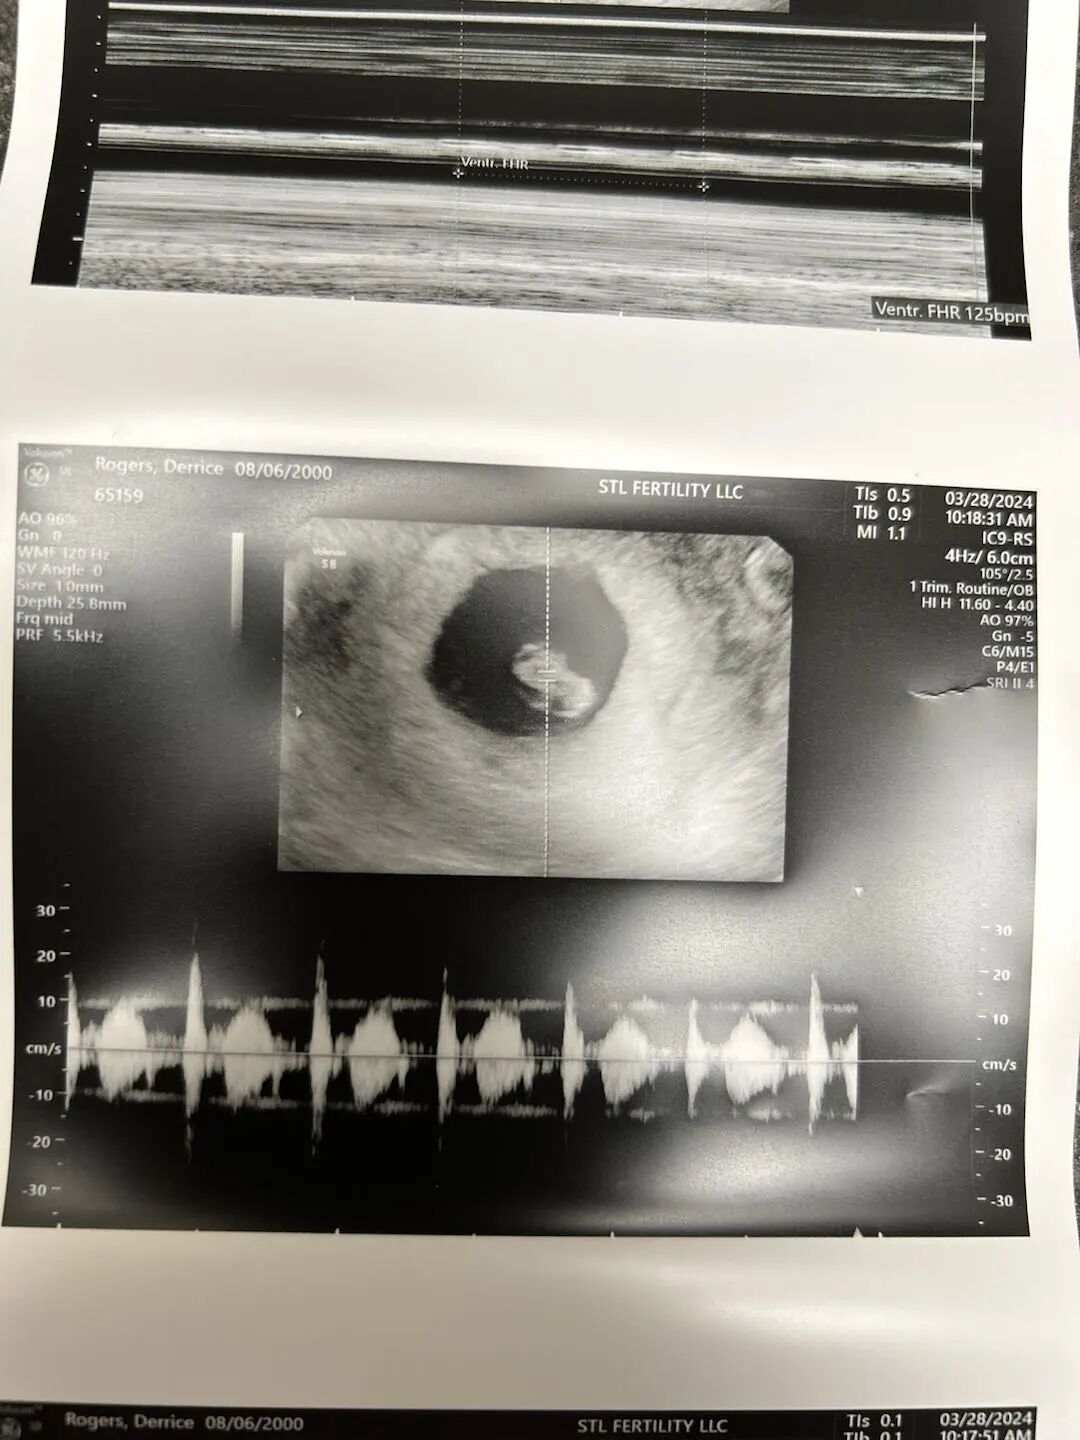

世界上最动听的声音之一毫无疑问就是宝宝的心跳!爱妈D在她的首次B超检查,宝宝已经成功着床,这个小小的生命正在稳步成长,值得庆祝的时刻~

从孕期的开始,爱妈D就表现出极高的配合度,遵循医嘱,更新日常,确保一切都能为宝宝的健康成长创造最佳条件。这份对宝宝的细致呵护最终带来了值得庆祝的结果。期待下次再见到宝宝的成长!